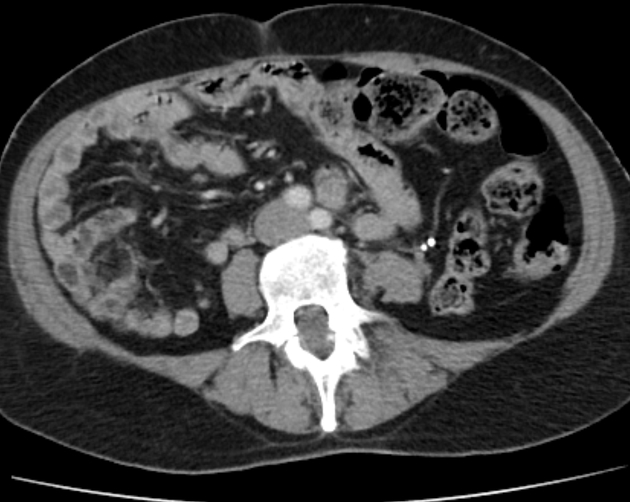

Modern technologies, such as multislice computed tomography (MSCT) combined with intravenous contrast, played a key role in unveiling the full picture. The use of this imaging technique helped expose not just an increased vascular pattern but also a large, irregular rectal lesion with uneven internal contours. These imaging findings triggered a deep investigation into whether the lesion was a mere hemangioma or something more complicated like a cancerous formation.

One of the most notable aspects of this case is the interplay between different imaging techniques. The blend of colonoscopy and multislice computed tomography provided a comprehensive view of the vascular anomalies in the rectum. While colonoscopy mapped out the mucosal surface and identified areas of potential pathology, MSCT dove deeper into the submucosal layers.

Combining these methods allowed clinicians to piece together a much more detailed image of the lesion’s anatomy and vascular supply. The fact that the lesion was supplied by both pararectal and parametrial blood vessels pointed towards an abnormal angiomatous supply, which further confirmed the complexity of the condition.